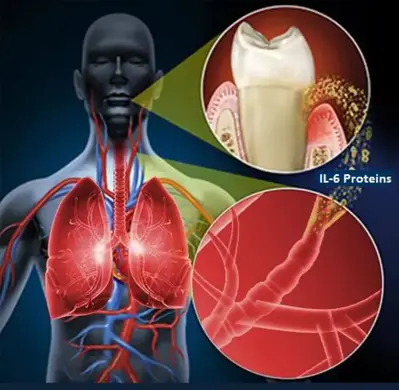

دندانپزشکی ایمن برای بیماران قلبی از آن جهت حیاتی است که این بیماران به دلیل شرایط پزشکی خاص خود در معرض خطرات بیشتری در طول درمانهای دندانی هستند. بیماریهای لثه مانند پریودنتیت میتوانند التهاب سیستمیک را افزایش دهند و به مشکلات قلبی عروقی منجر شوند. طبق مطالعهای در Circulation (Lockhart et al., 2012):

“Periodontal disease may contribute to the pathogenesis of atherosclerosis through systemic inflammation and endothelial dysfunction.”

ترجمه: بیماریهای پریودنتال ممکن است از طریق التهاب سیستمیک و اختلال عملکرد اندوتلیال به پاتوژنز آترواسکلروز کمک کنند (منبع).

این مطالعه نشان میدهد که عفونتهای دهانی میتوانند خطر بیماریهای قلبی را افزایش دهند. بنابراین، دندانپزشکی ایمن برای بیماران قلبی نیازمند محیطی مجهز به تجهیزات احیاء قلبی-ریوی و تیم درمانی آموزشدیده است، مانند آنچه در کلینیک نیکان دنت ارائه میشود (دندانپزشکی بیماران قلبی).

- خطر عفونت: عفونتهای دهانی میتوانند به قلب منتقل شوند و خطر اندوکاردیت عفونی را افزایش دهند.